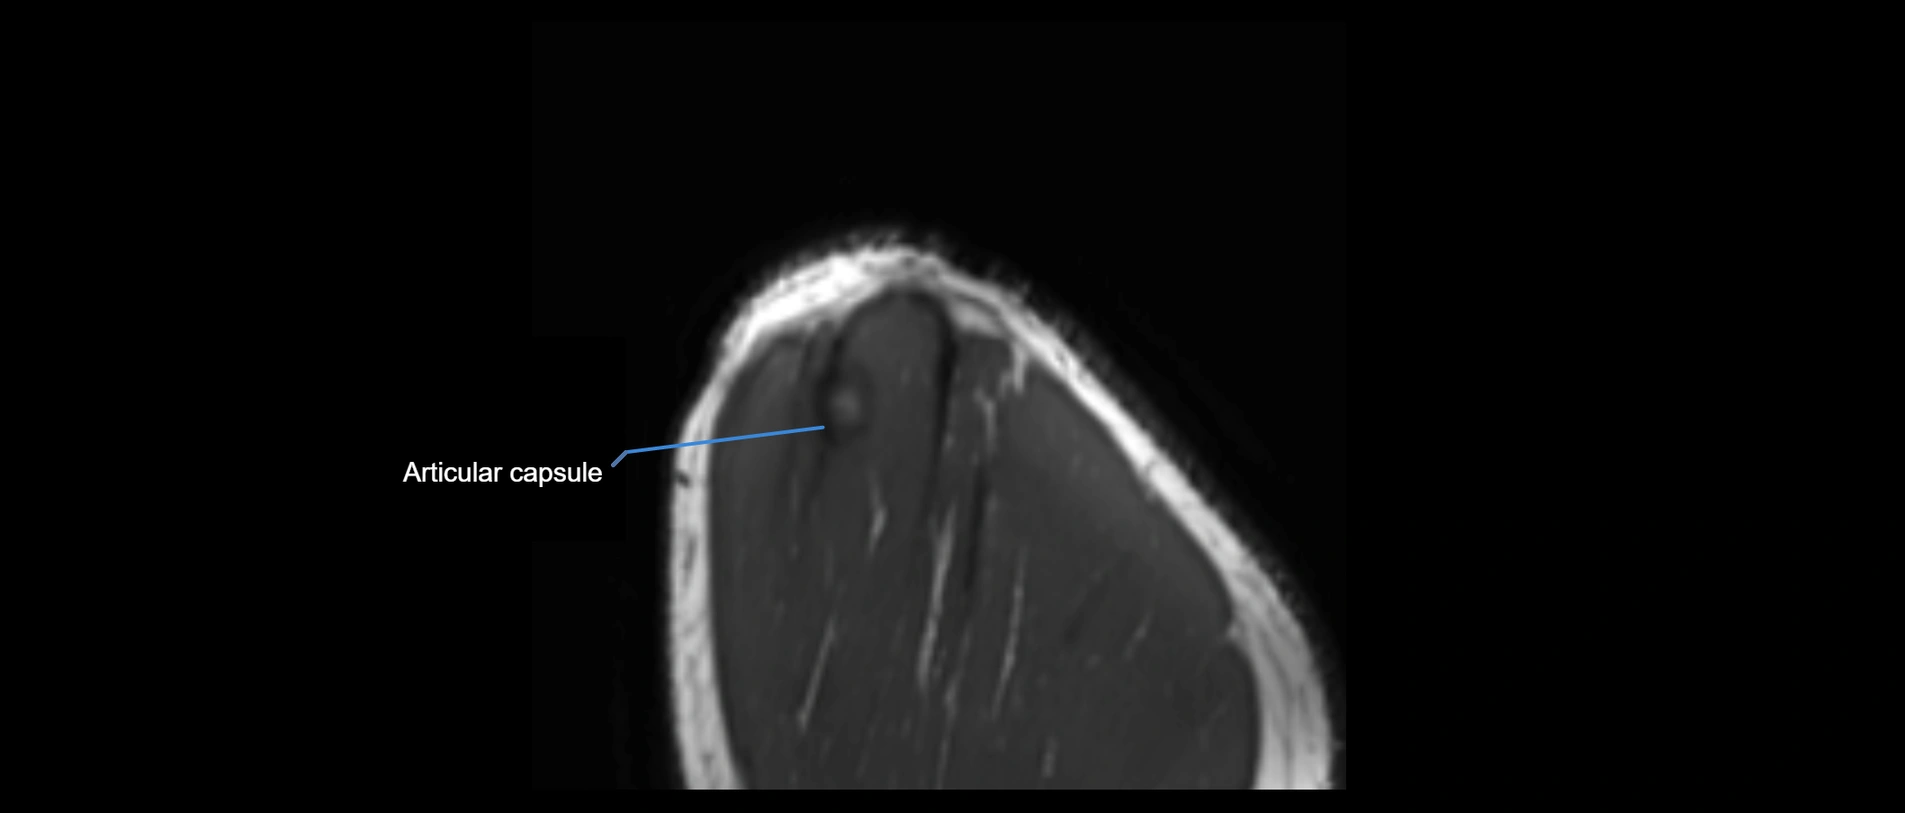

CT image

image